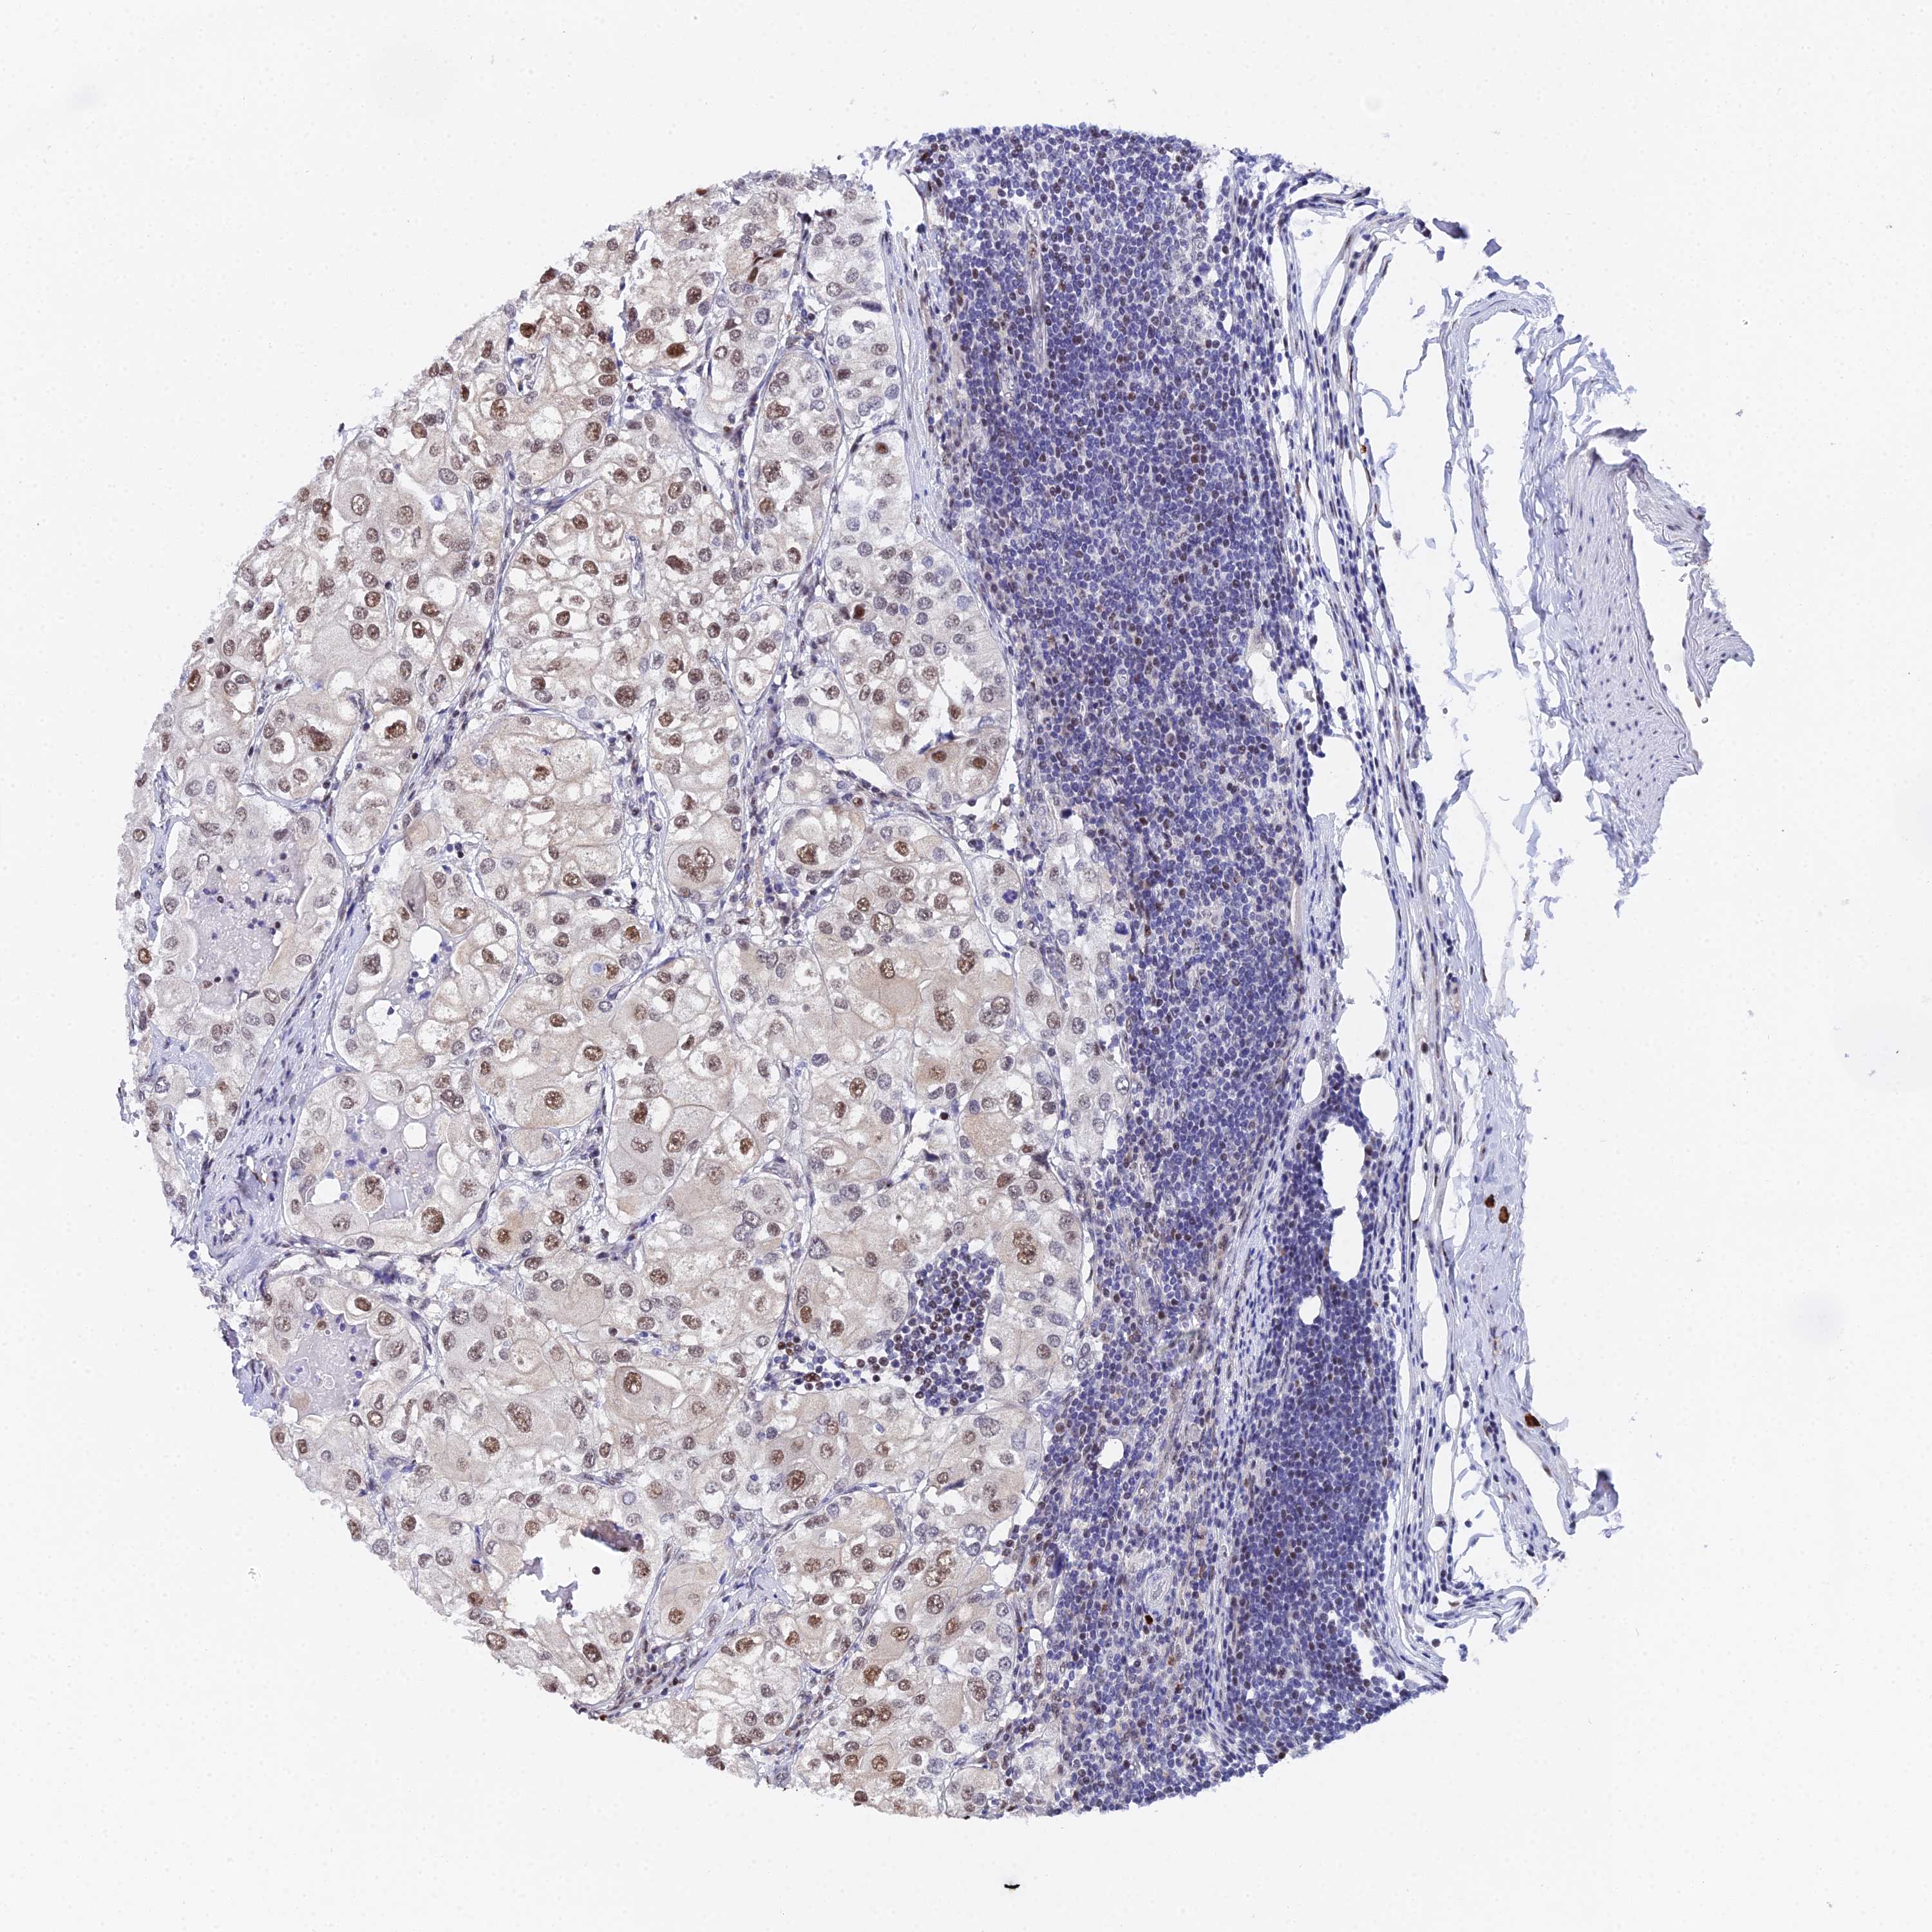

UROTHELIAL CANCER - Protein expressioni

A mouse-over function shows sample information and annotation data. Click on an image to view it in a full screen mode. Samples can be filtered based on level of antibody staining by selecting one or several of the following categories: high, medium, low and not detected. The assay and annotation is described here.

Antibody stainingi

Antibody staining in the annotated cell types in the current human tissue is reported as not detected, low, medium, or high, based on conventional immunohistochemistry profiling in selected tissues. This score is based on the combination of the staining intensity and fraction of stained cells.

Each image is clickable and will lead to virtual microscopy that enables deeper exploration of all samples and also displays staining intensity scores, fraction scores and subcellular localization as well as patient and tissue information for each sample.

Antibody HPA045889

Staining

High

Medium

Low

Not detected

Intensity

Strong

Moderate

Weak

Negative

Quantity

>75%

75%-25%

<25%

None

Location

Nuclear

Cytoplasmic/membranous

Cytoplasmic/membranous,nuclear

Urothelial carcinoma, High grade

Urothelial carcinoma, Low grade